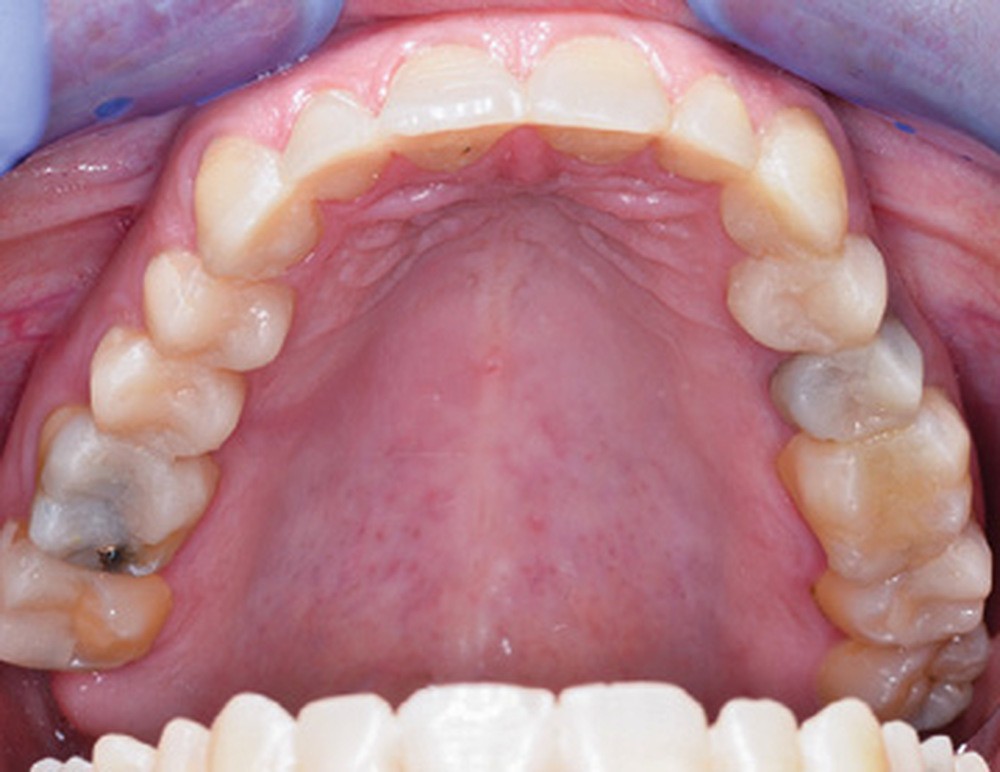

Mme V. est adressée au cabinet dentaire pour une réhabilitation de son sourire. À l’examen clinique, elle présente des usures sur l’ensemble de son maxillaire (fig. 17 et 18). Après évaluation du décalage OIM-ORC, une position de référence en relation centrée avec une dimension verticale augmentée est enregistrée. Pour valider cette position, il est demandé au laboratoire de réaliser un wax-up virtuel. Ce dernier est validé puis transféré en bouche pour essayage (fig. 19 et 20).

Ce mock-up est équilibré puis transformé en projet provisoire pour trois mois afin de s’assurer de la stabilité, du confort masticatoire et de l’esthétique. Au terme de ces trois mois, une empreinte de la situation est réalisée ainsi que l’enregistrement de l’occlusion ; enfin les secteurs postérieurs sont préparés pour recevoir des overlays. L’ensemble des informations (position et forme) est repris au sein du laboratoire pour dessiner les prothèses d’usage. Ces dernières seront produites par usinage, puis maquillées avant d’être envoyées au cabinet pour assemblage par collage sous champ opératoire (fig. 21 à 23).